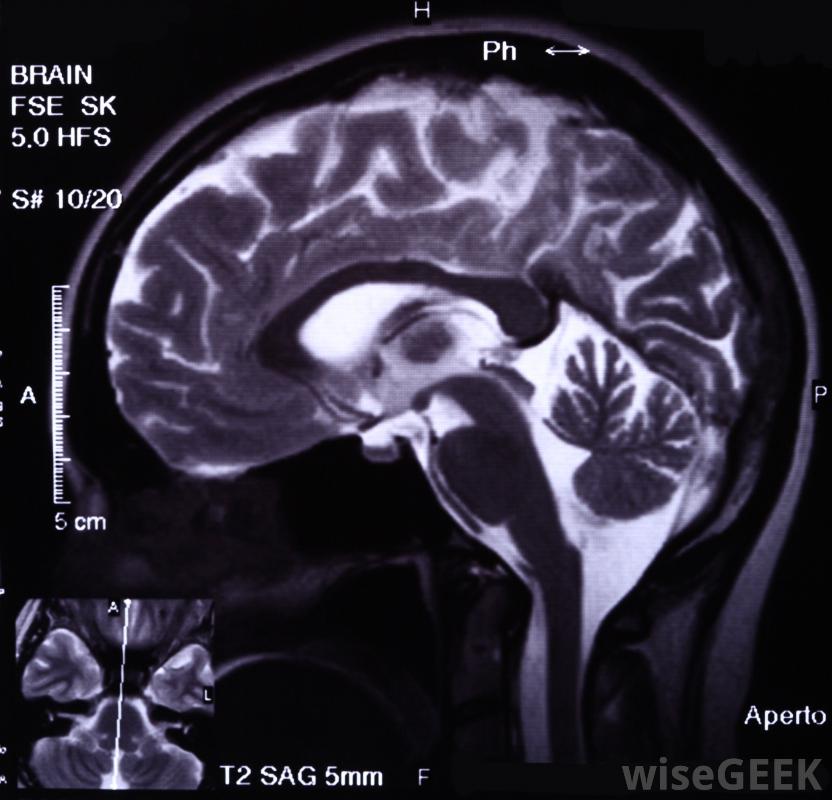

腦膜瘤手術治療腦膜瘤的方法有很多種,根據手術類型的不同,病人可能需要在全身麻醉下進行開顱手術,而其他患者可能在整個手術過程中保持清醒和警覺。患者應與外科醫生討論可用的選項,然后再選擇最適合的方案。有些患者會腦膜瘤手術時需要全身麻醉,而其他人則不需要。腦膜瘤是在大腦周圍的物質上形成的腫瘤,在腦膜瘤手術之前,我們將進行一系列的影像學研究,以進一步了解腫瘤及其位置,以確定是否它是可操作的。醫學成像掃描,如磁共振成像,用于定位和測量腫瘤最微創的方法是伽瑪刀手術,靶向放射治療病人的大腦,殺死腫瘤細胞對于這種類型的腦膜瘤手術,患者的頭部將被擰入一個金屬框架內,在顱骨周圍形成四個小切口。當伽瑪刀用于直接照射顱骨的右側區域時,患者處于清醒狀態。后續掃描將用于確認腫瘤已經消失。風險可能包括腫脹,可能手術刀是一種小而鋒利的刀,在外科手術中用來做切口腦膜瘤手術的其他微創方法包括通過鼻內鏡手術進入腫瘤。為了舒適和安全,患者將被置于麻醉下,風險略高于伽瑪刀手術,因為病人除了顱內腫脹外,還會發生感染。對于顱底等疑難部位的腫瘤,可能需要更具侵襲性的切口才能到達腫瘤,而且病人的風險也會增加。在某些情況下,腦膜瘤手術必須在重度麻醉下進行,神經外科醫生要打開并暴露大腦如果外科醫生能在腦膜瘤手術中成功地切除整個腫瘤,患者可能會獲得極好的結果,手術治愈率約為85%如果整個腫瘤不能切除,病人可能需要額外的治療,如放射療法來破壞它,并且有復發的風險。部分切除被認為是不可治愈的腫瘤仍然是有益的,因為它可以延長病人的壽命,提高生活質量如果外科醫生能在腦膜瘤手術中成功地切除整個腫瘤,患者可能會獲得非常好的結果。